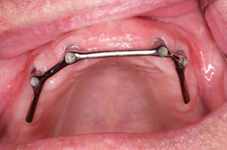

Třmeny

Kulové attachmenty

Sub-Tec Locator®

S pomocí zubních implantátů můžeme díky různým kotevním systémům (třmeny, kulové hlavy, Locatory) zajistit stabilitu a držení protézy nebo při použití většího počtu implantátů zhotovit pevné náhrady – můstky nalepené nebo našroubované na pevno na implantáty.